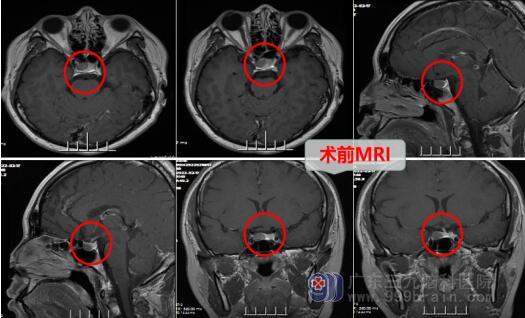

入院后,主管医生邓心情为她安排了头部MR检查,结果显示垂体右侧占位性病变,考虑是垂体腺瘤,垂体泌乳素高达339.00ug/L。大外科首席专家、神经外十科主任欧阳辉教授详细为佳佳及其家属讲述了病情及治疗方案,家属对佳佳脑袋里长了肿瘤非常担忧。欧阳教授说:“佳佳的这个肿瘤在脑外科是很常见,一般是良性肿瘤,不过要接受手术治疗,手术方案有两种:一种是经鼻子做,没有伤口,另外一种是开颅做,两种手术方式的技术都很成熟,但现在多倾向于经鼻微创手术,不必太过于担心。”家属听到欧阳教授这么一说心里也轻松了不少。

完善各项检查之后,2月18日在全麻下行内镜经鼻碟垂体腺瘤切除术。术后复查MR检查提示:内镜经鼻碟垂体瘤切除术+颅底重建术后改变,复查PRL为0.73ug/L,病理诊断为垂体神经内分泌肿瘤,免疫组化结果为泌乳激素细胞腺瘤。